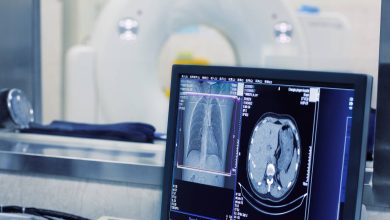

şüa diaqnostikası və radiologiya

Şüa Diaqnostikası: Elmi Əsasları, Tətbiq Sahələri

Müasir tibbin əsas dayaqlarından biri diaqnostik texnologiyalardır. Bu texnologiyaların içərisində şüa diaqnostikası xüsusi əhəmiyyətə malikdir. İnsan bədəninin daxili orqanlarının görünmədən,…